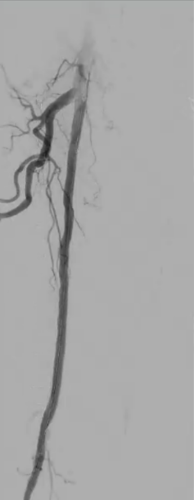

79-year-old male presented with severe claudication and intermittent rest pain of the right leg. Angiography showed a long occlusion of the SFA (Figure 1).

Procedure summary

Predilatation performed with plain angioplasty balloon. Next, three Passeo™-18 Lux™ DCB were used to cover the entire occluded segment, followed by a Pulsar™-18 T3 Bare-Metal Stent.